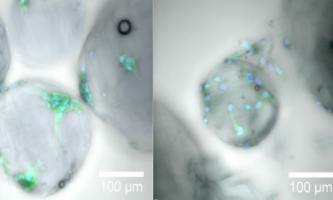

CICATRISATION : La motilité des kératinocytes prédit leur capacité de régénération